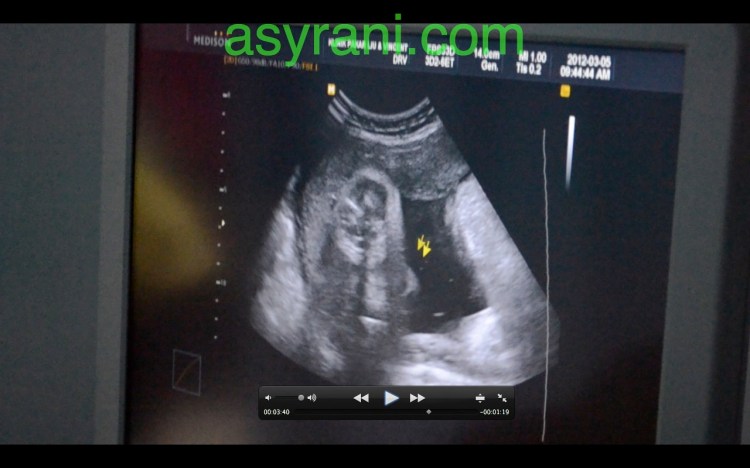

Gambar ini untuk ketika mengukur lilitan abdomen (waist)

Bacaan yang diperoleh setelah mengukur